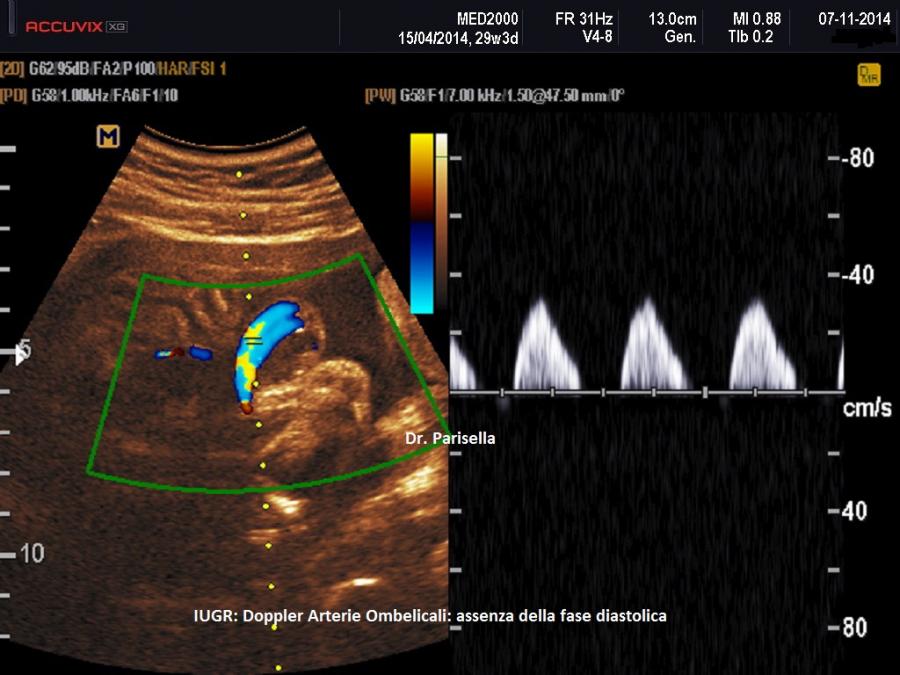

Arterie Uterine e Arterie Ombelicali - La flussimetria delle arterie uterine ha validità prevalente tra la 20a e la 24a settimana di gestazione (RCOG Green-top Guideline No. 31). Nel primo trimestre di gravidanza quando le arterie spirali invadono il trofoblasto le arterie uterine passano da vasi ad alta resistenza a vasi a bassa resistenza con conseguente aumento del flusso sanguigno; ciò permette di stabilire un flusso a bassa resistenza adeguato alla perfusione della placenta. Se questo processo, che si completa intorno alla 20° settimana di gestazione, non si verifica normalmente la mancata trasformazione delle arterie uterine da vasi ad alta resistenza in vasi a bassa resistenza condiziona una inadeguata invasione trofoblastica delle arterie spirali con conseguente circolazione ad alta resistenza ed aumento del PI nelle arterie uterine. In presenza di un difetto di crescita la persistenza di un PI medio delle arterie uterine elevato (PI medio > 95° percentile per epoca gestazionale) è associata a insufficienza placentare ( Levytska K et al., 2017 ). La eventuale successiva normalizzazione degli indici di velocità di flusso risulterà ancora associata ad un aumentato rischio di neonato FGR (RCOG Green-top Guideline No. 31). L’aumento del PI nelle arterie uterine provoca un aumento delle resistenze nella vascolarizzazione placentare con conseguente riduzione della superficie placentare disponibile per lo scambio di ossigeno e nutrienti (Burton GJ et al., 2019) cui segue un progressivo aumento del PI nelle arterie ombelicali (UAPI). Nel Feto il primo cambiamento emodinamico è una riduzione del flusso venoso ombelicale con conseguente ridistribuzione del flusso venoso dal fegato al cuore fetale, le dimensioni del fegato diminuiscono causando un ritardo di crescita della circonferenza addominale fetale che è il primo segno biometrico di Feto FGR. L’insufficienza vascolare placentare, inizialmente caratterizzata dall’aumento del UAPI, può peggiorare passando, nella fase terminale, da un flusso diastolico ridotto in arteria ombelicale (PED) ad un flusso assente (AED) o invertito (RED). L'assenza e/o la inversione del flusso telediastolico (ARED: absent or reverse end-diastolic flow) nelle arterie ombelicali è un segno importante di compromissione sia fetale che placentare rappresentando un importante predittore di danno cerebrale o di morte neonatale nei feti FGR.

Le Linee Guida del RCOG, SOGC e CNOGF raccomandano l'esecuzione della velocimetria Doppler dell'arteria ombelicale quale modalità primaria di monitoraggio delle gravidanze complicate da ritardo di crescita intrauterino in quanto in grado di ridurre la morbilità perinatale e anche al fine di valutare la necessità di anticipazione del parto. Secondo le Linee Guida SOGC e del CNOGF le anomalie tardive della velocimetria Doppler ombelicale (flusso telediastolico assente, AEDF, oppure flusso telediastolico invertito, REDF) rappresentano una indicazione all’espletamento del parto in caso di epoca gestazionale superiore alle 34 settimane. Secondo le Linee Guida RCOG il parto non deve essere espletato oltre la 37a settimana in caso di anomalie della velocimetria Doppler dell'arteria ombelicale.

-Monitoraggio > 26 settimane < 32 : In caso di Doppler-flussimetria dell'arteria ombelicale nella norma i controlli vanno effettuati ogni 2 settimane. In caso di Doppler-flussimetria dell’arteria ombelicale patologica con normale presenza di flusso in diastole (PED) i controlli devono essere settimanali con valutazione del liquido amniotico, flussimetria-Doppler e monitoraggio cardiotocografico, mentre la biometria va effettuata ogni 2 settimane. In caso di Doppler-flussimetria dell'arteria ombelicale patologica con alterazione del flusso in diastole (AED/RED) va effettuata anche la valutazione Doppler-flussimetrica del dotto venoso con attenzione all’onda a: se questa è assente o reverse è indicato l'espletamento del parto. I controlli vanno intensificati con valutazione del liquido amniotico e della Doppler-flussimetria ogni 2 giorni e monitoraggio cardiotocografico computerizzato fino anche a 2 volte al giorno.

Va effettuata profilassi con 12 mg di betametasone i.m. in due dosi somministrate a distanza di 24 ore e in caso di possibilità di espletamento del parto entro 12 ore è opportuno attuare anche la neuroprofilassi fetale con Magnesio solfato e.v. Per il timing e la modalità del parto a quest'epoca gestazionale in caso di Doppler-flussimetria ombelicale patologica (PED, AED, RED), si procede all'espletamento del parto prima delle 32 settimane se CTGc (computerizzata) patologica o se CTGc normale ma la flussimetria Doppler del dotto venoso è caratterizzata da assenza o reverse dell'onda a. Il parto va effettuato mediante taglio cesareo data l'epoca gestazionale precoce e le scarse riserve di questi feti (Ting JY et al., 2018).